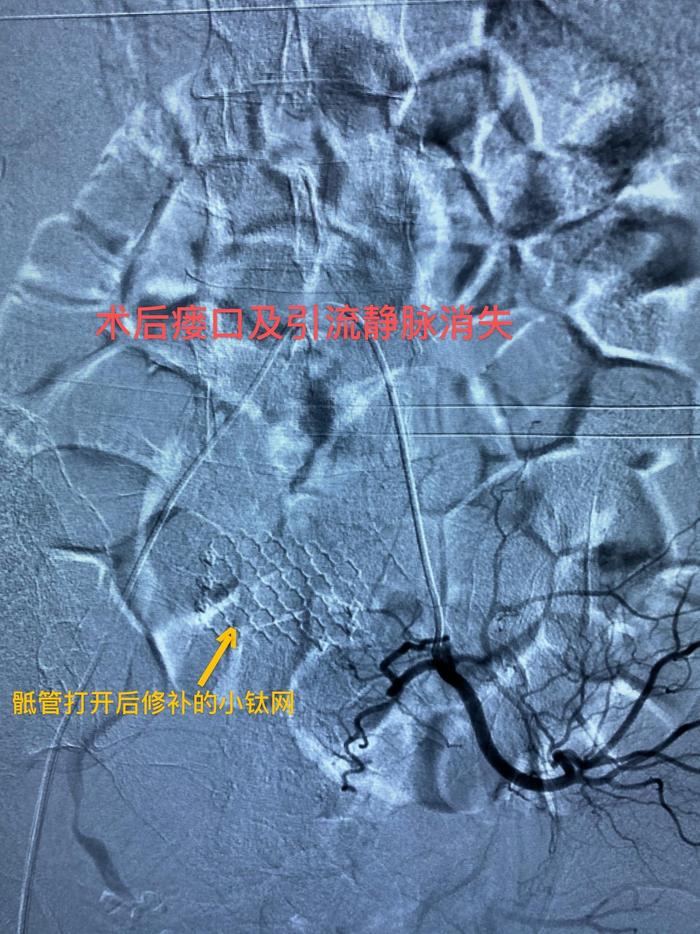

术中准确找到SDAVF瘘口及引流静脉术后复查DSA,SDAVF瘘口以及引流静脉完全不显影,患者双下肢肌力和感觉有很大进步,证实了手术的成功。